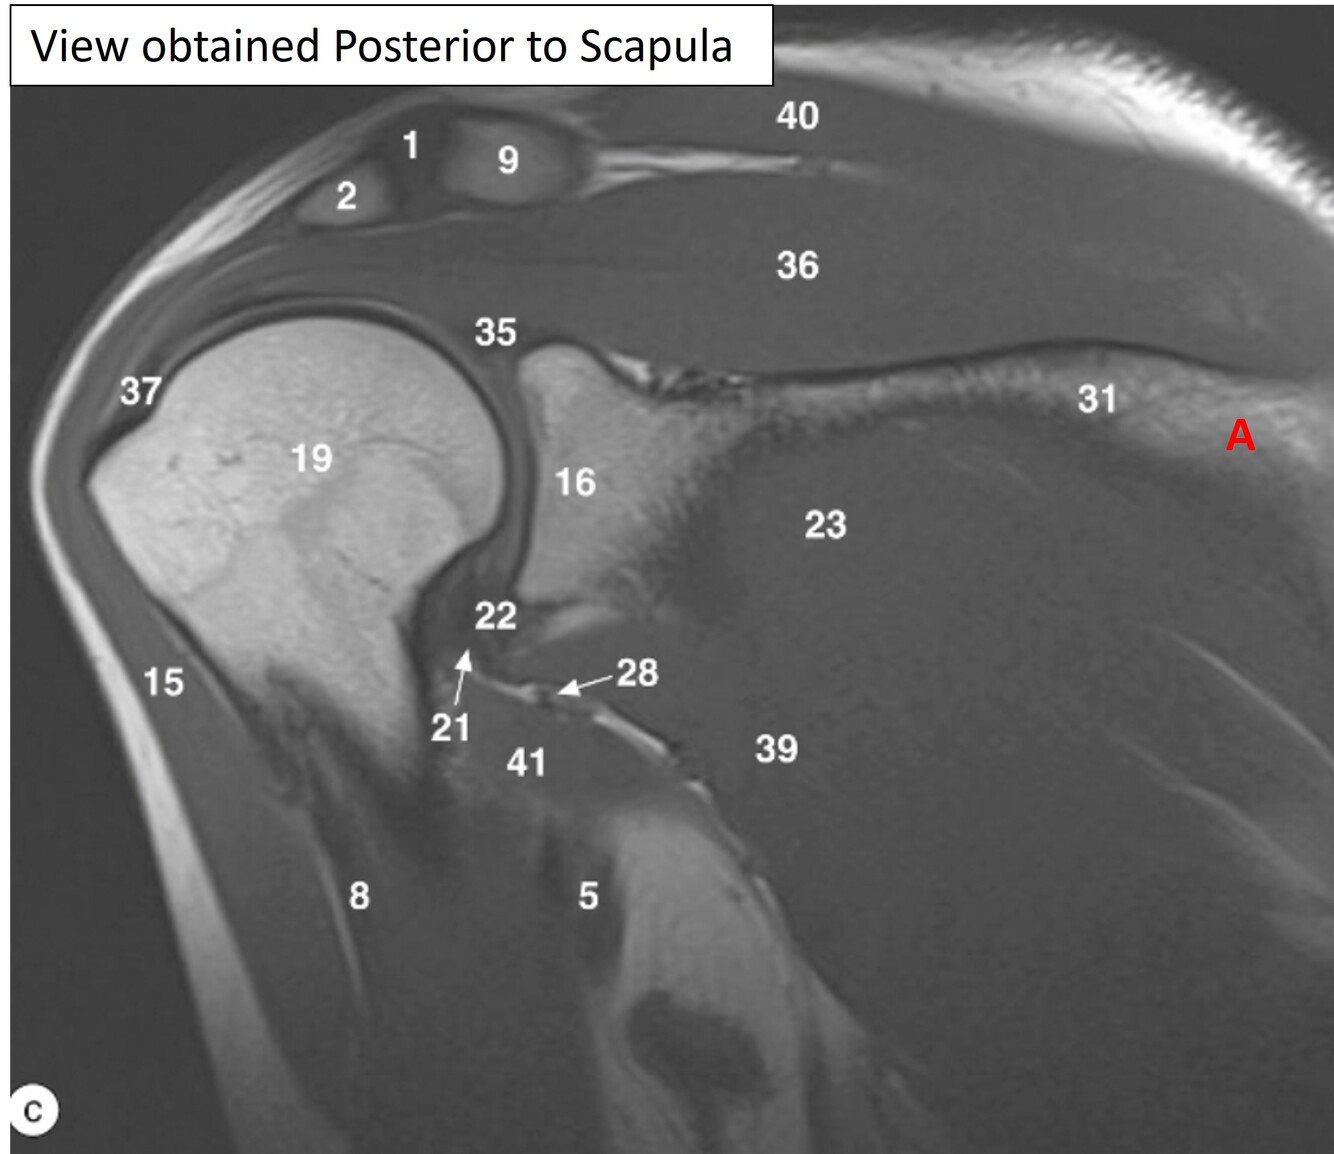

1=Rt. AC joint

2=Rt. Acromion of scapula

9=Rt. Clavicle (acromial end)

15=Rt. deltoid muscle

36-Rt. supraspinatous muscle

40=Rt. trapezius muscle

Label 23, 31,36,39,40

A

23=Rt. infraspinatus muscle

31=Spine of rt. scapula

36-Rt. supraspinatus muscle

39=Rt. teres minor

Q

Label a

Supraspinous fossa